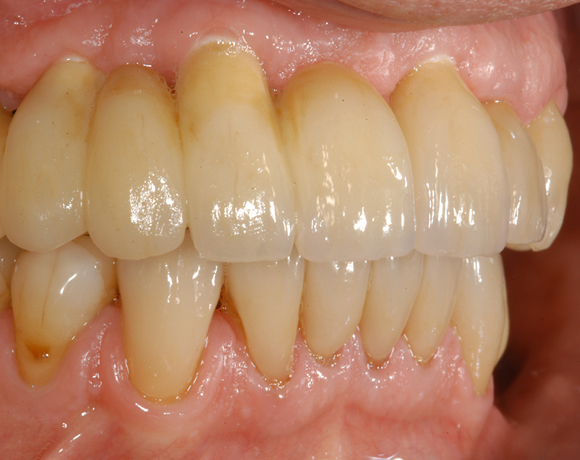

6 Implantate und viele Kronen und Brücken

Mit dem zweiteiligen vollkeramischen Implantat lassen sich auch große Lücken überbrücken.

Ein Projekt aus dem Jahr 2011

Im vorliegenden Patientenfall waren die Zähne 11 – 26 mit einer provisorischen Brücke versorgt, der Patient konnte damit aber nicht essen. Auch im Unterkiefer waren die vorhandenen Kronen und Brücken insuffizient. Es wurde eine komplette Neuversorgung für Ober- wie Unterkiefer geplant.